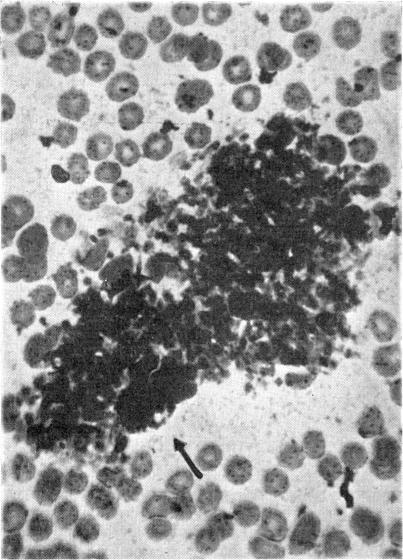

Observations on the effects, of a series of dextran sulphates of varying molecular weight on the formed elements of the blood in vitro.

Br J Pharmacol Chemother. 1953 Sep;8(3):340-7. doi: 10.1111/j.1476-5381.1953.tb00804.x.